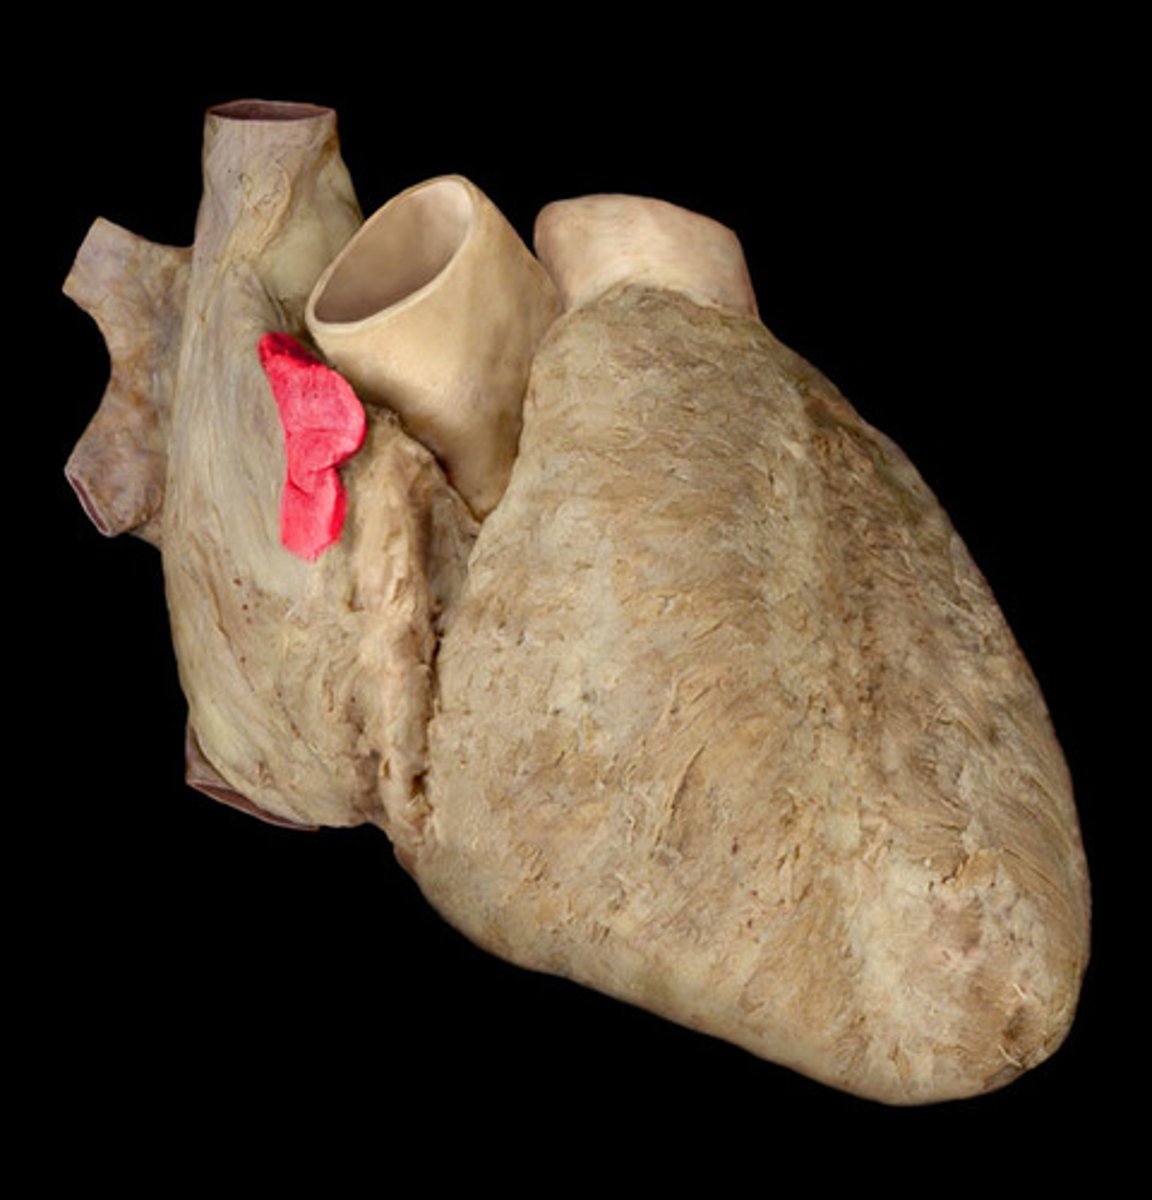

ligamentum arteriosum

vestige of the fetal ductus arteriosus, which shunted blood in the pulmonary trunk away from the lungs in the fetus